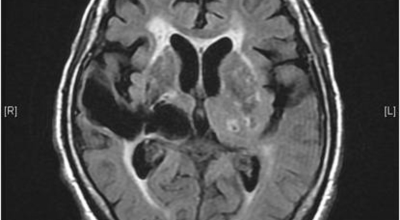

파킨슨병은 도파민 분비 신경 세포의 소실로 발생하는 질환으로 알려져 있는데요 도파민이란 뇌의 신경세포에서 만들어지는 물질로 세포와 세포 간의 신호를 전달하는데 이용되는 신경 전달 물질 중 한가지로 이 도파민이 감소함에 따라 파킨슨병이 걸린다고 하는데 이 도파민 세포가 떨어지는 이유는 아직 정확히 밝혀지지 않았다고 합니다.

파킨슨병이라는 것은, 퇴행성 뇌 질환으로 알츠하이머, 치매 다음으로 자주 나타나는 뇌 연관 질병으로 1817년 영국 병리학자 파킨슨이 보고 해서 그의 이름을 따서 병의 이름이 결정되었다고 합니다.파킨슨병에 걸릴 경우 일반적으로 40세 이후로 첫 증상이 나타나고 50세에 가장 많이 발생한는 것으로 알려져 있고 30세 이전에는 아주 드물지만 유전적으로 나타나는 경우도 있다고 합니다.